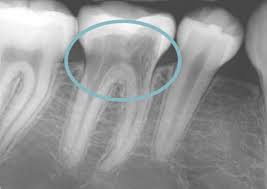

External root resorption treatment. If a dentist is able to spot the external symptoms and remove the cells causing damage in time you may not require any further dental care. Root resorption has been defined as the loss of dental hard tissue as a result of osteoclastic cell action 1 and can occur on both external and internal surfaces. If you can access then treatment with geristore or similar and possibly TCA for 1-4 minutes to remove tissue fragments.

The therapeutic measures which can regulate clastic activity include endodontic treatment the use of specific anticlastic agents such as Ledermix paste non-specific necrobiotic agents such as calcium hydroxide and trichloracetic acid surgery or root surface conditioners. External root resorptions are processes in which the loss of cementoblasts occurs causing the mineralized surfaces to be susceptible to the action of clastic cells. If you look at the tooth from the coronal view youll notice the location of the resorption is a little improved making it easy to understand why we call it external cervical resorption.

However if more of the tooth structure has been affected a filling or root canal therapy might be the treatment of choice. Although it is predominantly detected by radiography in some cases root resorption may be identified by clinical symptoms such as pain swelling and mobility of the tooth. Patient was willing to try to save the tooth and took the second option. Sometimes it may be possible to repair the damage to the tooth but in some cases the only solution is to extract the. A second opinion may be necessary. In cases where the resorptive process is already established root canal treatment can arrest the resorption and encourage hard tissue repair. External root resorptions are processes in which the loss of cementoblasts occurs causing the mineralized surfaces to be susceptible to the action of clastic cells. External resorption can be misdiagnosed. External cervical resorption treatment options vary depending on the severity of the situation.

External Resorption Treatment ConsiderationsPrognosis Favorable Questionable Unfavorable External Resorption Minimal loss of tooth structure Located cervically but above the crestal bone The lesion is accessible for repair Apical root resorption associated with a tooth exhibiting pulp necrosis and apical pathosis Minimal impact on restorability of tooth. What is the treatment for dental resorption. The therapeutic measures which can regulate clastic activity include endodontic treatment the use of specific anticlastic agents such as Ledermix paste non-specific necrobiotic agents such as calcium hydroxide and trichloracetic acid surgery or root surface conditioners. If you look at the tooth from the coronal view youll notice the location of the resorption is a little improved making it easy to understand why we call it external cervical resorption. If a dentist is able to spot the external symptoms and remove the cells causing damage in time you may not require any further dental care. Root canal crown gum surgery tooth removal extraction. The treatment of root resorption is basically root and or periodontal endodontic treatment depending on the.